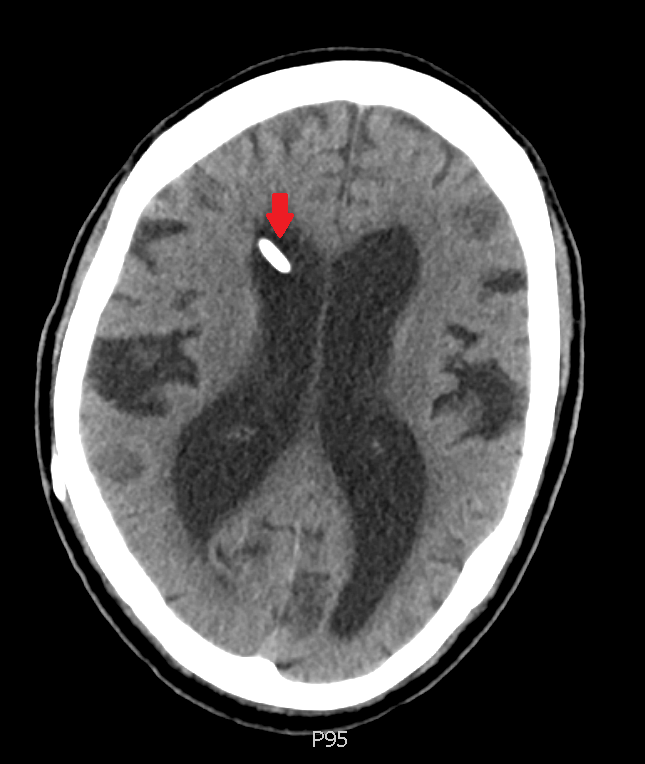

Axial CT

One of the key radiographic findings in NPH is enlarged ventricles, out of proportion to cortical atrophy. Remember that generalized brain atrophy can lead to hydrocephalus ex-vacuo, or large appearing ventricles simply as a result of diffuse volume loss. Look at the three images above – in each, the ventricles are much larger than expected.